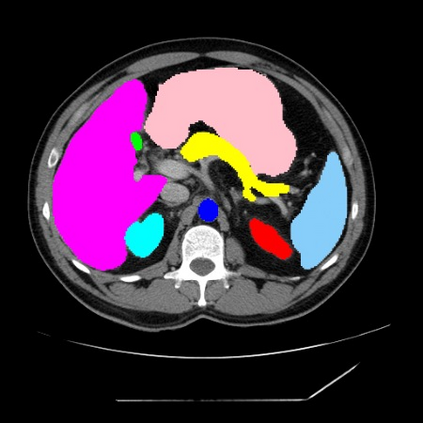

Integrating high-level semantically correlated contents and low-level anatomical features is of central importance in medical image segmentation. Towards this end, recent deep learning-based medical segmentation methods have shown great promise in better modeling such information. However, convolution operators for medical segmentation typically operate on regular grids, which inherently blur the high-frequency regions, i.e., boundary regions. In this work, we propose MORSE, a generic implicit neural rendering framework designed at an anatomical level to assist learning in medical image segmentation. Our method is motivated by the fact that implicit neural representation has been shown to be more effective in fitting complex signals and solving computer graphics problems than discrete grid-based representation. The core of our approach is to formulate medical image segmentation as a rendering problem in an end-to-end manner. Specifically, we continuously align the coarse segmentation prediction with the ambiguous coordinate-based point representations and aggregate these features to adaptively refine the boundary region. To parallelly optimize multi-scale pixel-level features, we leverage the idea from Mixture-of-Expert (MoE) to design and train our MORSE with a stochastic gating mechanism. Our experiments demonstrate that MORSE can work well with different medical segmentation backbones, consistently achieving competitive performance improvements in both 2D and 3D supervised medical segmentation methods. We also theoretically analyze the superiority of MORSE.